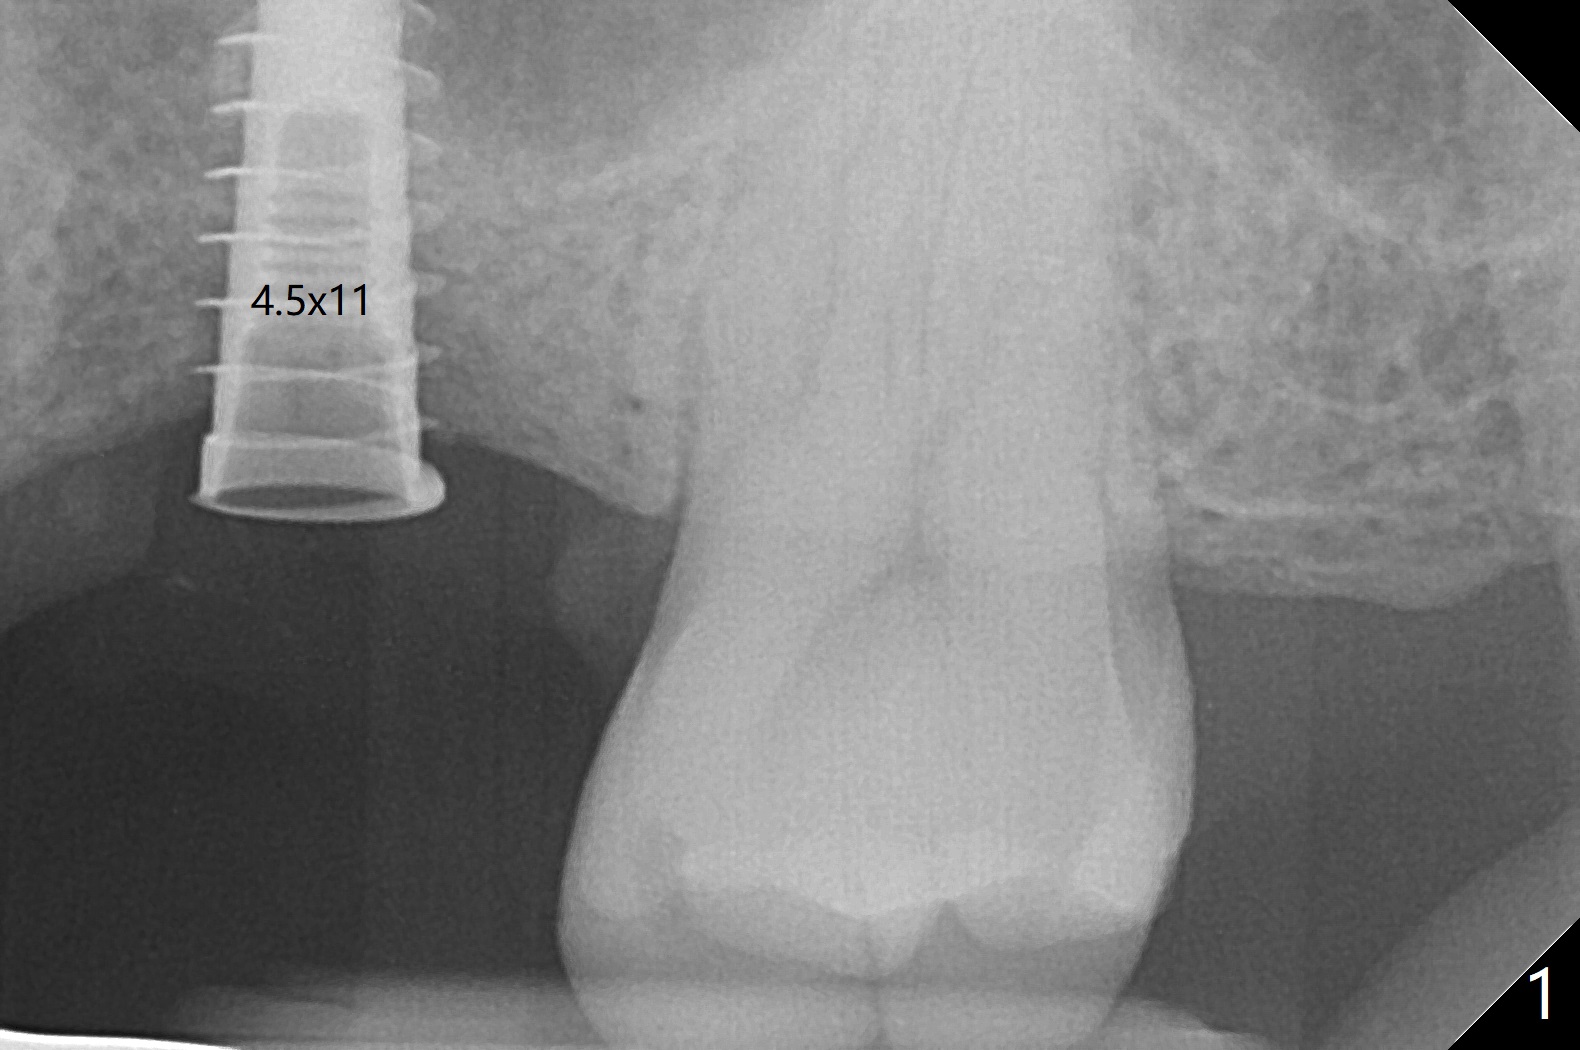

After using 4.5x5.3 mm and 3.5x7.3 mm drill at #14 with guide, the sinus floor is not perforated. When a 4.5x11 mm dummy implant is placed to the 2nd line (12 mm offset), the sinus membrane is perforated (Fig.1). A piece of PRF membrane and sticky bone are pushed into the sinus in an attempt for repair. A shorter implant is placed (5x7.3 (instead of 8.5) mm, Fig.2,3,5, as compared to Fig.3) to reduce postop sinus infection. In fact incision reveals palatal bony concavity. When the implant is placed, there is mild palatal thread exposure. With incision instead of tissue punch, it is easy to place bone graft over the small defect (Fig.3 *). The wound dehisces and heals 2 weeks postop (Fig.6). There is bone loss 6.5 months postop (Fig.7 *), corresponding to palatal thread exposure. After decortication and periosteal underscoring, cortical allograft mixed with ~.25 cc GEM21S is placed (Fig.8 *).